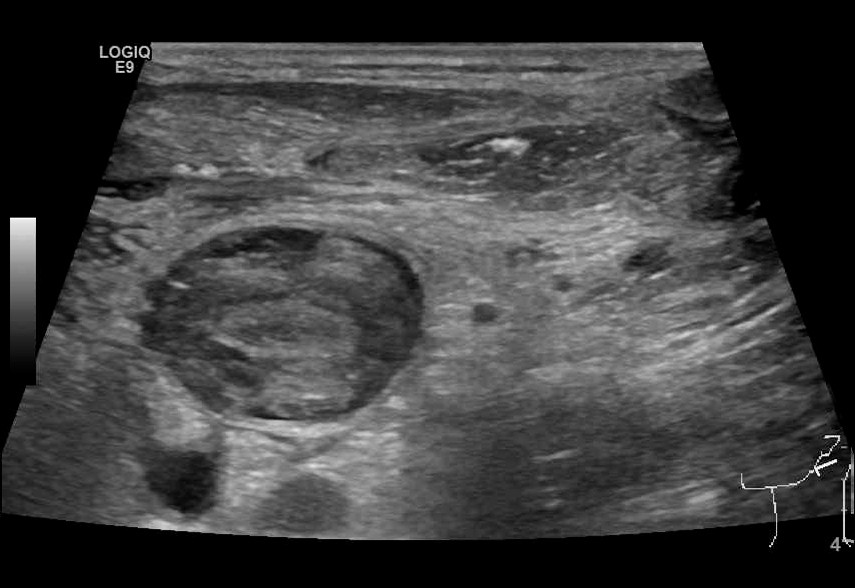

Ultralydundersøkelsen av halsen viste imidlertid en betydelig trombemasse som nærmest totalokkluderte venstre v. jugularis interna og v. subclavia (figur 1 og 2). Den totale utbredelsen av tromben kunne ikke fremstilles med ultralyd, og det ble derfor supplert med en CT-venografi, som viste utbredt trombosering som omfattet nedre del av venstre v. jugularis (fra nivå med carotisbifurkaturen), v. subclavia og v. brachiocephalica frem til innløpet av v. cava superior (figur 3). Det var multiple luftbobler fordelt i trombemassen. Vi mistenkte at dette var forårsaket av bakterier, og dermed at en infisert trombe var fokus for pasientens infeksjon.

Ultralyd er en ikke-invasiv og kostnadseffektiv metode for å påvise trombemasser. Dessverre er den suboptimal for diagnostikk av tromber lokalisert dypt under mandibula eller clavicula. CT-venografi er derfor av mange anbefalt som foretrukket undersøkelsesmetode (6). I vårt tilfelle fikk vi med CT-venografi identifisert hele utbredelsen av trombemassen samt påvist karakteristiske luftbobler som underbygget mistanken om infisert trombe.

Funn av små intravenøse luftbobler på CT er ikke unormalt, da små luftbobler kan bli injisert sammen med kontrastvæsken. Luftbobler kan også sees i det mesenterielle eller portalvenøse systemet grunnet iskemi eller infeksjon. Luftbobler inne i en trombemasse er derimot sjeldent, og funnet forsterker derfor mistanken om infisert trombe (7).